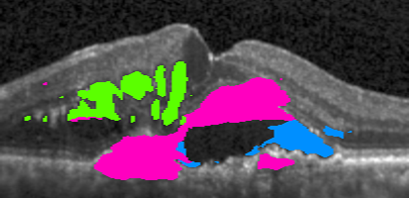

Input 666 121212 242424 Full Access Target

Refer to caption Refer to caption Refer to caption Refer to caption Refer to caption Refer to caption

Baseline

Our approach – Multi-label Deep Supervision

MIL Baseline

Deeply Supervised MIL

Our approach – Mean-Taught Deep Supervision

Figure 4: Segmentation progression when increasing the number of pixel-wise annotated masks from 666 to 121212, 242424, and full access. The upper two methods leverage only pixel-wise masks while the remaining three methods have access to weak annotations (image-level labels).

4.6 Qualitative results

In \figreffig:qualitative, we show segmentation results as more annotations are added for the Baseline and Multi-label Deep Supervision models as well as some semi-weakly supervised results. Comparing the first two rows, we observe the advantageous effect of our deep supervision technique, especially in the low-data setting. Similarly, when comparing our deep supervision in Mean-Taught models (bottom row) to the rest, we directly see in column two and three that our models nicely segment the fluid regions, even with extremely few samples while other methods fail severely.